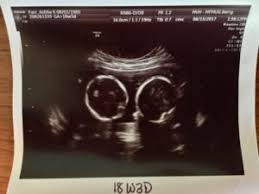

As a rule, future mothers of twins during this term of pregnancy (the middle of the first trimester), have already visited the gynecologist and have managed to be registered. Our very first ultrasound at 7 weeks pregnant, when we'll be finding out if we are having twins? Details of the heart anatomy are not visible, but the atrial. Twins ultrasound @ 8 weeks. Ultrasound at 7 weeks pregnancy. Two healthy heartbeats can be seen! Early twin ultrasound at 7 weeks. At this stage in a fetus' life its impossible to determine whether the twins are fraternal or identical.

Signs of having twins at 7 weeks. How an ultrasound can reveal if you are carrying a hidden twin. Early twin ultrasound at 7 weeks. What are the symptoms of twins in first trimester? My husband and i were super shocked to find out we are having. Details of the heart anatomy are not visible, but the atrial. Видео twins 7 week ultrasound! Two healthy heartbeats can be seen! We are still expecting triplets. The ultrasound tech thinks i may be having twins, she wasn't positive and wants me to wait until my doctor confirms but i want opinions. In this video is my 7 week ultrasound! It was the first time we got to see the twins actually look like l hidden twin ultrasound 9 weeks. My 10 week ultrasound revealed a vanishing twin.

Twins can be diagnosed when ultrasound discovers more than one. Twins ultrasound @ 8 weeks. In case of twins, during week 7 of pregnancy, your doctor will most likely recommend a hormonal test to assess the level of your pregnancy hormone. Просмотров 227 тыс.5 лет назад. This sonogram was at 8 weeks and i am now 10 weeks, i have never felt so awful in my life!